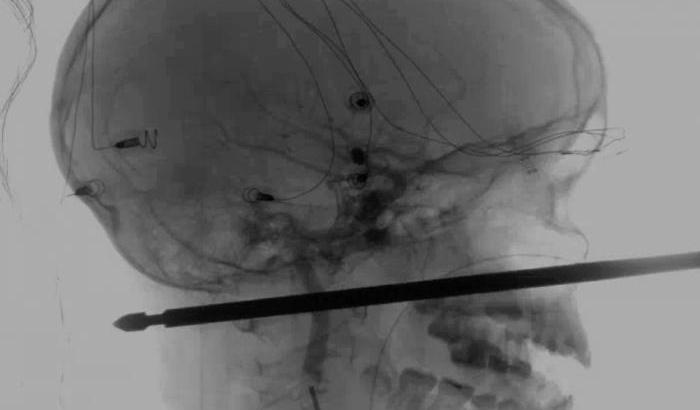

Chi ha fede può anche accendere un cero: e infatti gli stessi medici non esitano a definire «miracoloso» l’esito del bizzarro e inquietante incidente di cui è stato vittima un bambino di 10 anni del Missouri. Trafitto alla testa da parte a parte da uno spiedino, infatti, non solo è sopravvissuto, ma si riprenderà completamente.

Sabato, Xavier Cunningham stava giocando su una casa sull’albero a Harrisonville quando è stato attaccato da uno sciame di vespe. Nel tentativo di sfuggirgli è caduto dalla pianta e, arrivato al suolo, lo spiedino metallico per la carne gli si è conficcato accanto al naso e gli ha penetrato il cranio fino a sbucare dalla nuca.

Ai medici è stato presto chiaro quanta fortuna nella sfortuna avesse avuto Xavier: «Quell’affare gli ha risparmiato l’occhio, il cervello e la spina dorsale», ha spiegato il direttore di neurochirurgia endovascolare, Koji Ebersole. L’unica preoccupazione rimanevano i vasi sanguigni maggiori del collo, che potevano essere danneggiati.

L’estrazione doveva avvenire in maniera estremamente precisa perché lo spiedino non era cilindrico ma squadrato e gli spigoli avrebbero potuto causare gravi danni. Fortunatamente tutto è andato bene: «“Miracoloso” è il termine appropriato per descrivere quanto è successo», afferma Ebersole. Xavier, che si trova ancora in ospedale, si riprenderà completamente.